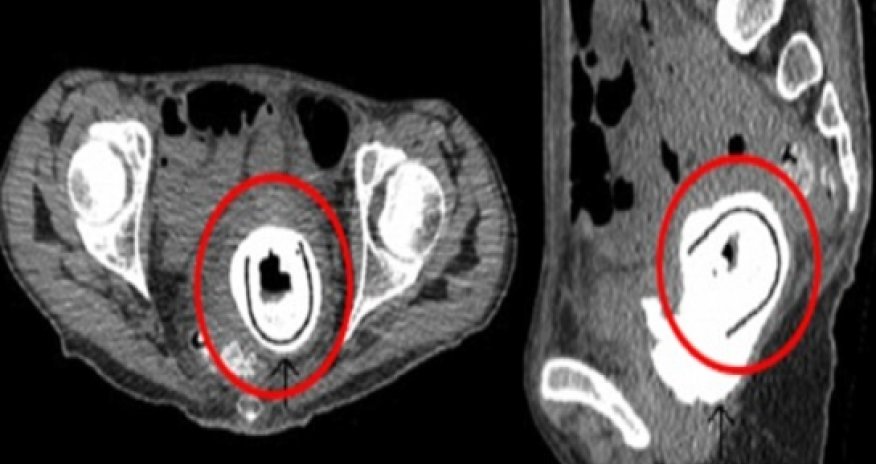

A Scottish woman walked around with a five-inch sex toy inside her for 10 years without realising, doctors have reported.

The 38-year-old woman arrived at hospital complaining of severe weight loss, shaking and lethargy. She had also experienced mild incontinence for 'a few weeks'.On further examination, doctors were shocked to discover a strange foreign body protruding into her bladder from her vagina.Surgical removal of the item at Aberdeen Royal Infirmary revealed it to be a five inch (11cm)-long sex toy.Medical staff were even more taken back when the woman revealed she had used the sex toy with her partner ten years ago. She also admitted she was under the influence of alcohol at the time - and claimed she couldn't remember removing it or not. The woman had a normal IQ, no signs of depression or psychosis and had not been subject to any abuse, according to the case report.But the sex toy had caused her potentially life-threatening damage.The woman was suffering from a rare 'vesicovaginal fistula' – an abnormal tract which allows urine to flow into the vagina. She also had an obstructive uropathy, where a blockage in the bladder causes urine to back up into the kidneys. After removing the sex toy, doctors managed to repair the damage and the woman was later discharged.One doctor at the hospital, who was not willing to comment on the patient's specific case, confirmed it was highly unusual for such a large foreign object to go unnoticed in the majority of instances - by patients or their partners.This is because the vagina is full of nerve endings and is extremely sensitive, he says.The patient’s case - reported in The Journal of Sexual Medicine - is the first time a sex toy has been left inside a woman for as long as a decade.However it’s not the longest time an object has remained hidden in a woman’s vagina. A review of similar cases uncovered a report of a woman who'd had a foreign object lodged in her vagina for 35 years.Other bizarre items that have been discovered include a hairspray cap, a cylindrical tin container, a plastic cup and a child’s toy. One case study from 2009 even describes how doctors discovered a 3x5 cm foreign body in a 72-year-old woman’s vagina - but she and the doctors were unable to work out what is was.Doctors say people usually deny knowledge of the existence or origin of such items when they are initially discovered, due to embarrassment or fear of recrimination.The practice is common in patients suffered from Münchausen syndrome – a psychiatric condition where the person feigns symptoms in order to gain attention or sympathy.Psychiatric disorders, alcohol abuse, and child abuse are also common among these patients.(dailymail.co.uk)Bakudaily.az